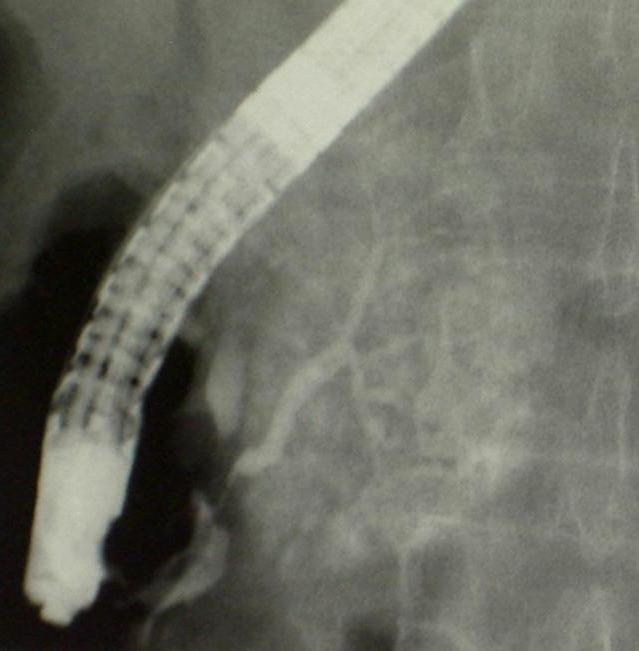

The perihilar form of the malignant tumor originating from the biliary ducts is called Klatskin tumor.

This type of malignant tumor is detected in the background of an ictreus of unknown origin unfortunatelly even more frequently. In certain cases ERCP is useful in the cytologic sampling, but sometimes an imaging method guided biopsy is needed for the histological verification. According to the localisation, the following types are known (Bismuth-classification):

In case of an inoperable tumor or a high hilar localisated Klatskin tumor (Figure 37), the bridging of the certain stenosis can be tryed by percutaneous intervention from the direction of both lobes (left and right sided double hepatic duct drainage and stent implant).

Figure 37: Klatskin tumor, PTC, punction from left biliary duct of the liver

Additional relevant details can be found in the nonvascular intervention chapter.